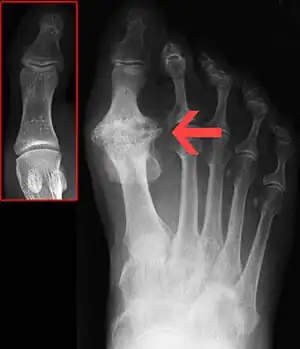

| Xray showing hallux rigidus marked by the arrow, with normal big toe within the inset | |